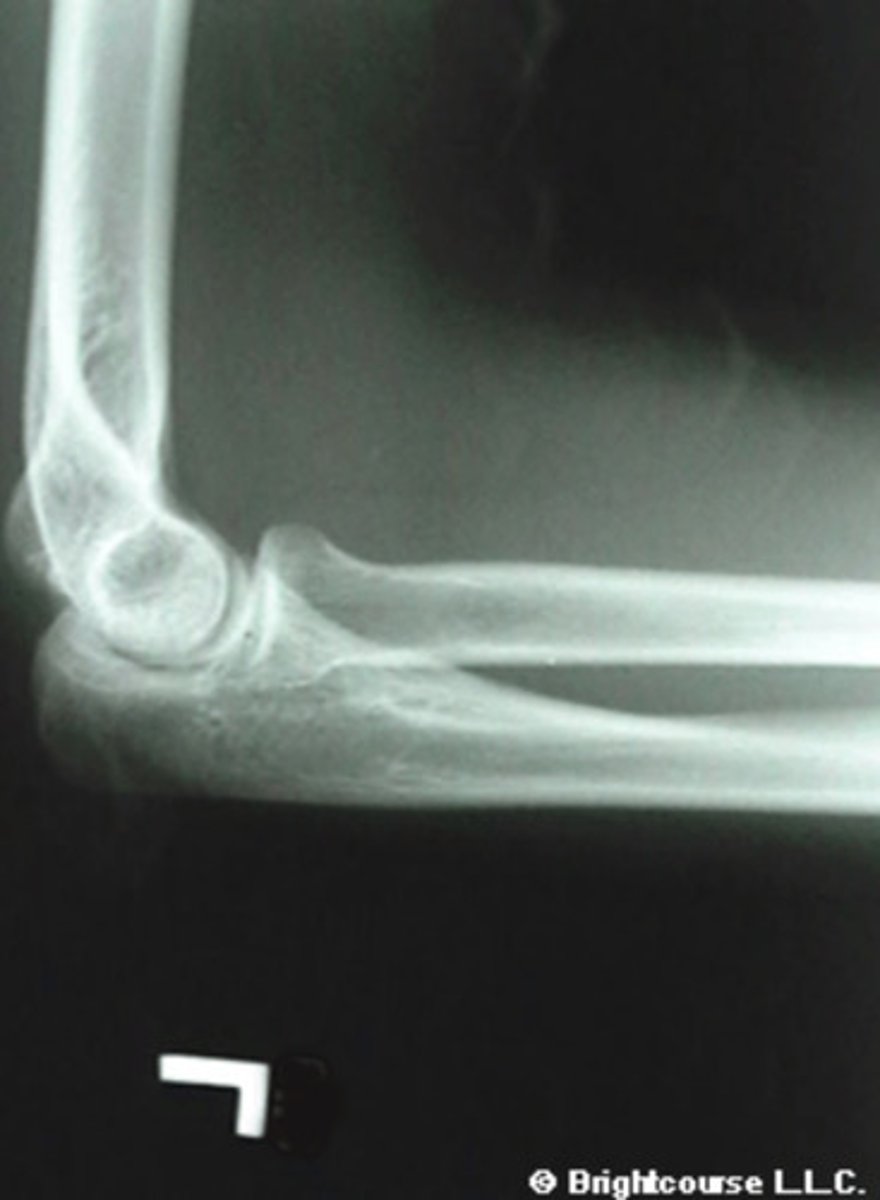

Lateral elbow

What is the name of the radiographic projection?